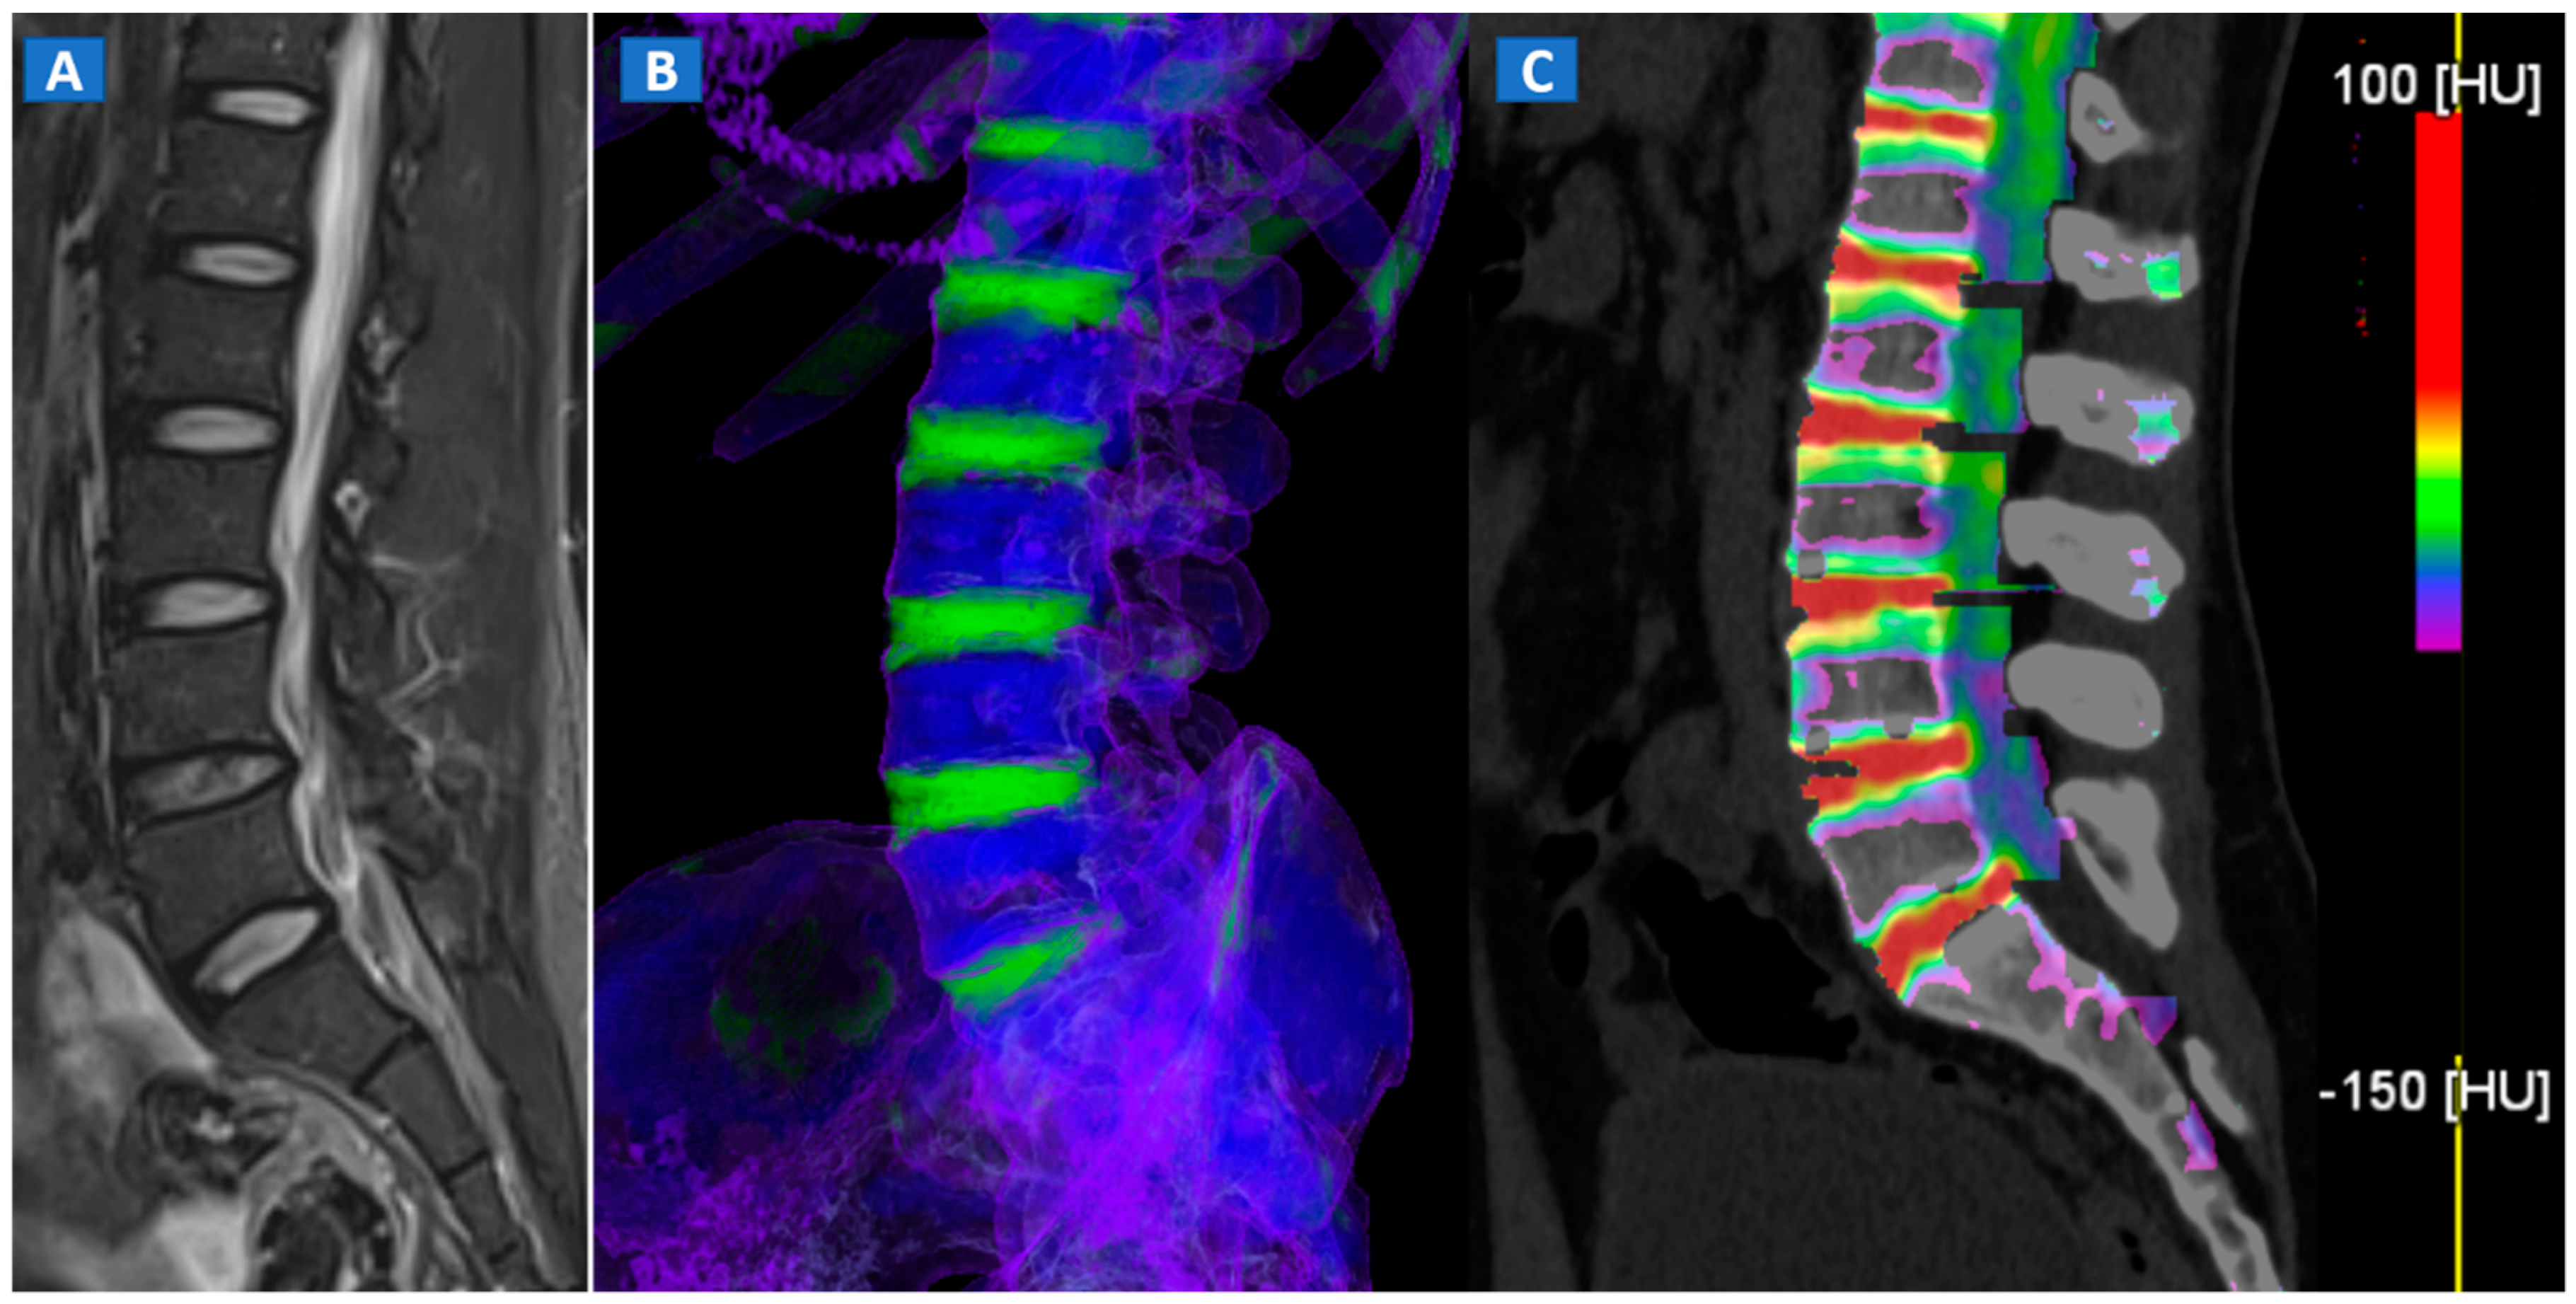

DECT 3D images are usually evaluated first, coding BME in shades of green and coding normal bone in blue (Figure 1). These images serve to provide a clear visual overview of the whole anatomical area, prior to any focus on specific findings. 3D images are usually more sensitive for depicting BME than 2D images (Figure 2). 2D images are analyzed by super-imposing the DE-specific information onto conventional grayscale morphological images (thickness, 1 mm; increment, 1 mm). Usually, a color lookup table is applied, which codes BME in shades ranging from green-yellow to orange-red (Figure 1C), with a range of densities set between −150 and 100 HU (Figure 1C). Superimposed color-coded maps are utilized only when density values are above the −50 HU cut-off. This approach can be useful in distinguishing between severe and mild BME (Figure 2). Additional windowing can also be carried out by increasing or decreasing the level of super-imposition of color-coded images in order to confirm or rule out subtler findings (Figure 2).

Figure 1.

A 43-year-old male with low back pain following high-energy trauma, with no vertebral fractures. On the sagittal STIR MRI image (A), all lumbar vertebral bodies show a normal shape and signal intensity. On the 3D DECT image, on the para-sagittal plane (B), normal vertebral bodies are coded in blue, whereas density increases, due to increased water content, are coded in green. As expected, the normal intervertebral discs are coded in green. In addition, normal cortical bone is also coded in green, due to an incomplete subtraction process. On the corresponding 1 mm sagittal 2D DECT image (C) there is a color lookup table that codes bone marrow and areas of oedema in shades of green-yellow to orange-red. DE-specific information has been fused with conventional grayscale morphological images (thickness, 1 mm; increment, 1 mm). The range of densities is set between −150 and 100 HU, with underlying normal bone visualized without any superimposition for density values below the −50 HU cut-off.

4. The Spine

In cases of high-energy trauma, DECT images can help to rule out vertebral oedema, and reduce the reading time (Figure 1). When multiple vertebral fractures are present, DECT can identify fresh fractures that are typically characterized by the presence of BME (Figure 2). Furthermore, high resolution CT images can also be used to evaluate fine anatomical details such as transverse processes or posterior arches.